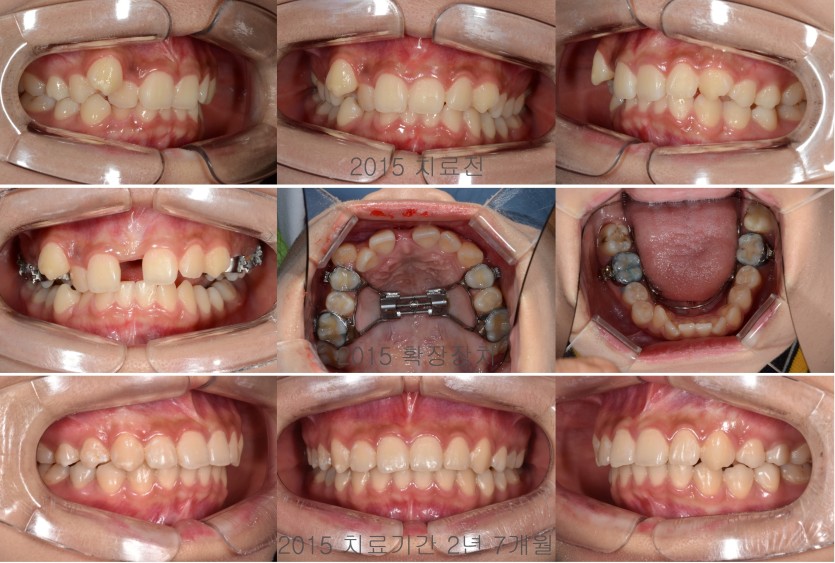

상악을 급속확장하여 덧니 배열공간을 확보한 경우 134회

상악 우측 송곳니의 배열공간이 상당히 부족한 덧니였지만 소구치를 발치하지 않고

상악을 급속확장하는 장치를 이용해서 상악 골격을 확장하면서 덧니를 배열할 수 있습니다.

덧니를 비발치 확장의 방법으로 해결하기 위해서는 안모의 평가, 치조골의 평가, 배열을 위해 필요한 공간의 분석등이 꼼꼼히 이뤄져야 합니다.